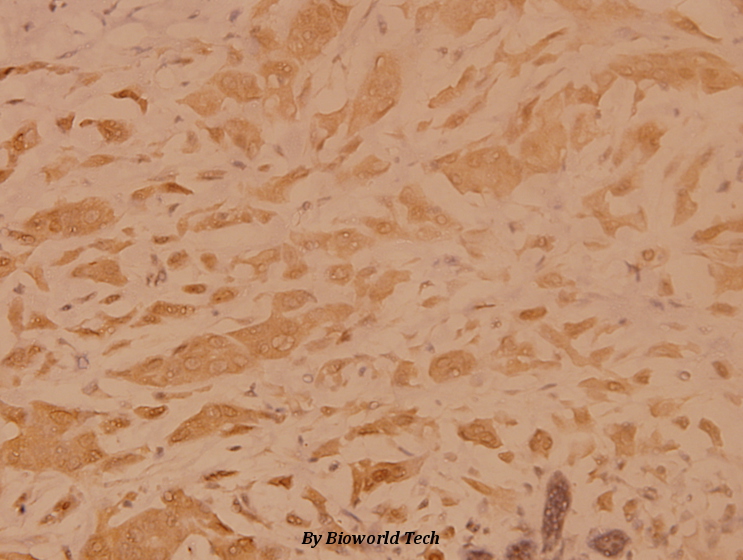

![TRADD antibody [N2C3] detects TRADD protein at cytoplasm by immunohistochemical analysis. Sample: Paraffin-embedded human endometrial carcinoma. TRADD stained by TRADD antibody [N2C3] (GTX113042) diluted at 1:500. Antigen Retrieval: Citrate buffer, pH 6.0, 15 min](https://www.genetex.com/upload/website/prouct_img/normal/GTX113042/GTX113042_40086_20181207_IHC-P_w_23060500_418.webp)